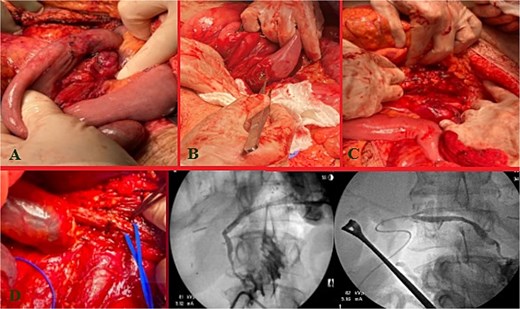

Massive transfusion protocol was initiated, and he was taken to the operating room for an emergent exploratory celiotomy. Upon entrance into the abdominal cavity, a 10 cm hematoma, along the transverse colon consistent with a mesenteric arterial hemorrhage, was identified and rapidly controlled (Fig. 1A). A Cattell-Braasch maneuver was employed, mobilizing the right colon, and a Kocher maneuver to fully explore the duodenum, revealing a AAST Grade II D2 injury that was repaired in 2 layers (Fig. 1B). The pancreatic head and tail had AAST Grade II injuries with multiple arterial bleeds that were controlled with suture ligation and argon beam coagulation (Fig. 1C).

Index operation. A: Transverse colon hematoma. B: Duodenal (D2) injury. C: Pancreatic head and tail vascular injury. D: Common bile duct and intraoperative cholangiogram through the common bile duct and cystic duct.

On initial inspection, the GB infundibulum was contused, and there was bile staining along the porta hepatis. The common bile duct (CBD) was identified and appeared grossly normal. However, due to the proximity of the pancreatic head injury and bile staining, we performed an intraoperative cholangiogram (IOC) through a mid-portion CBD needle ductotomy, to spare the GB as a potential conduit if a biliary repair was required. The initial IOC did not reveal an injury to the CBD and did not demonstrate extravasation of contrast (Fig. 1D). The needle ductotomy was closed with a running 3–0 Monocryl stitch. As we were concluding the damage control laparotomy a persistent, mild, bile staining within and along the porta hepatis, was noted. The possibility of a more proximal extrahepatic bile duct injury was raised as the common bile needle ductotomy closure remained intact.